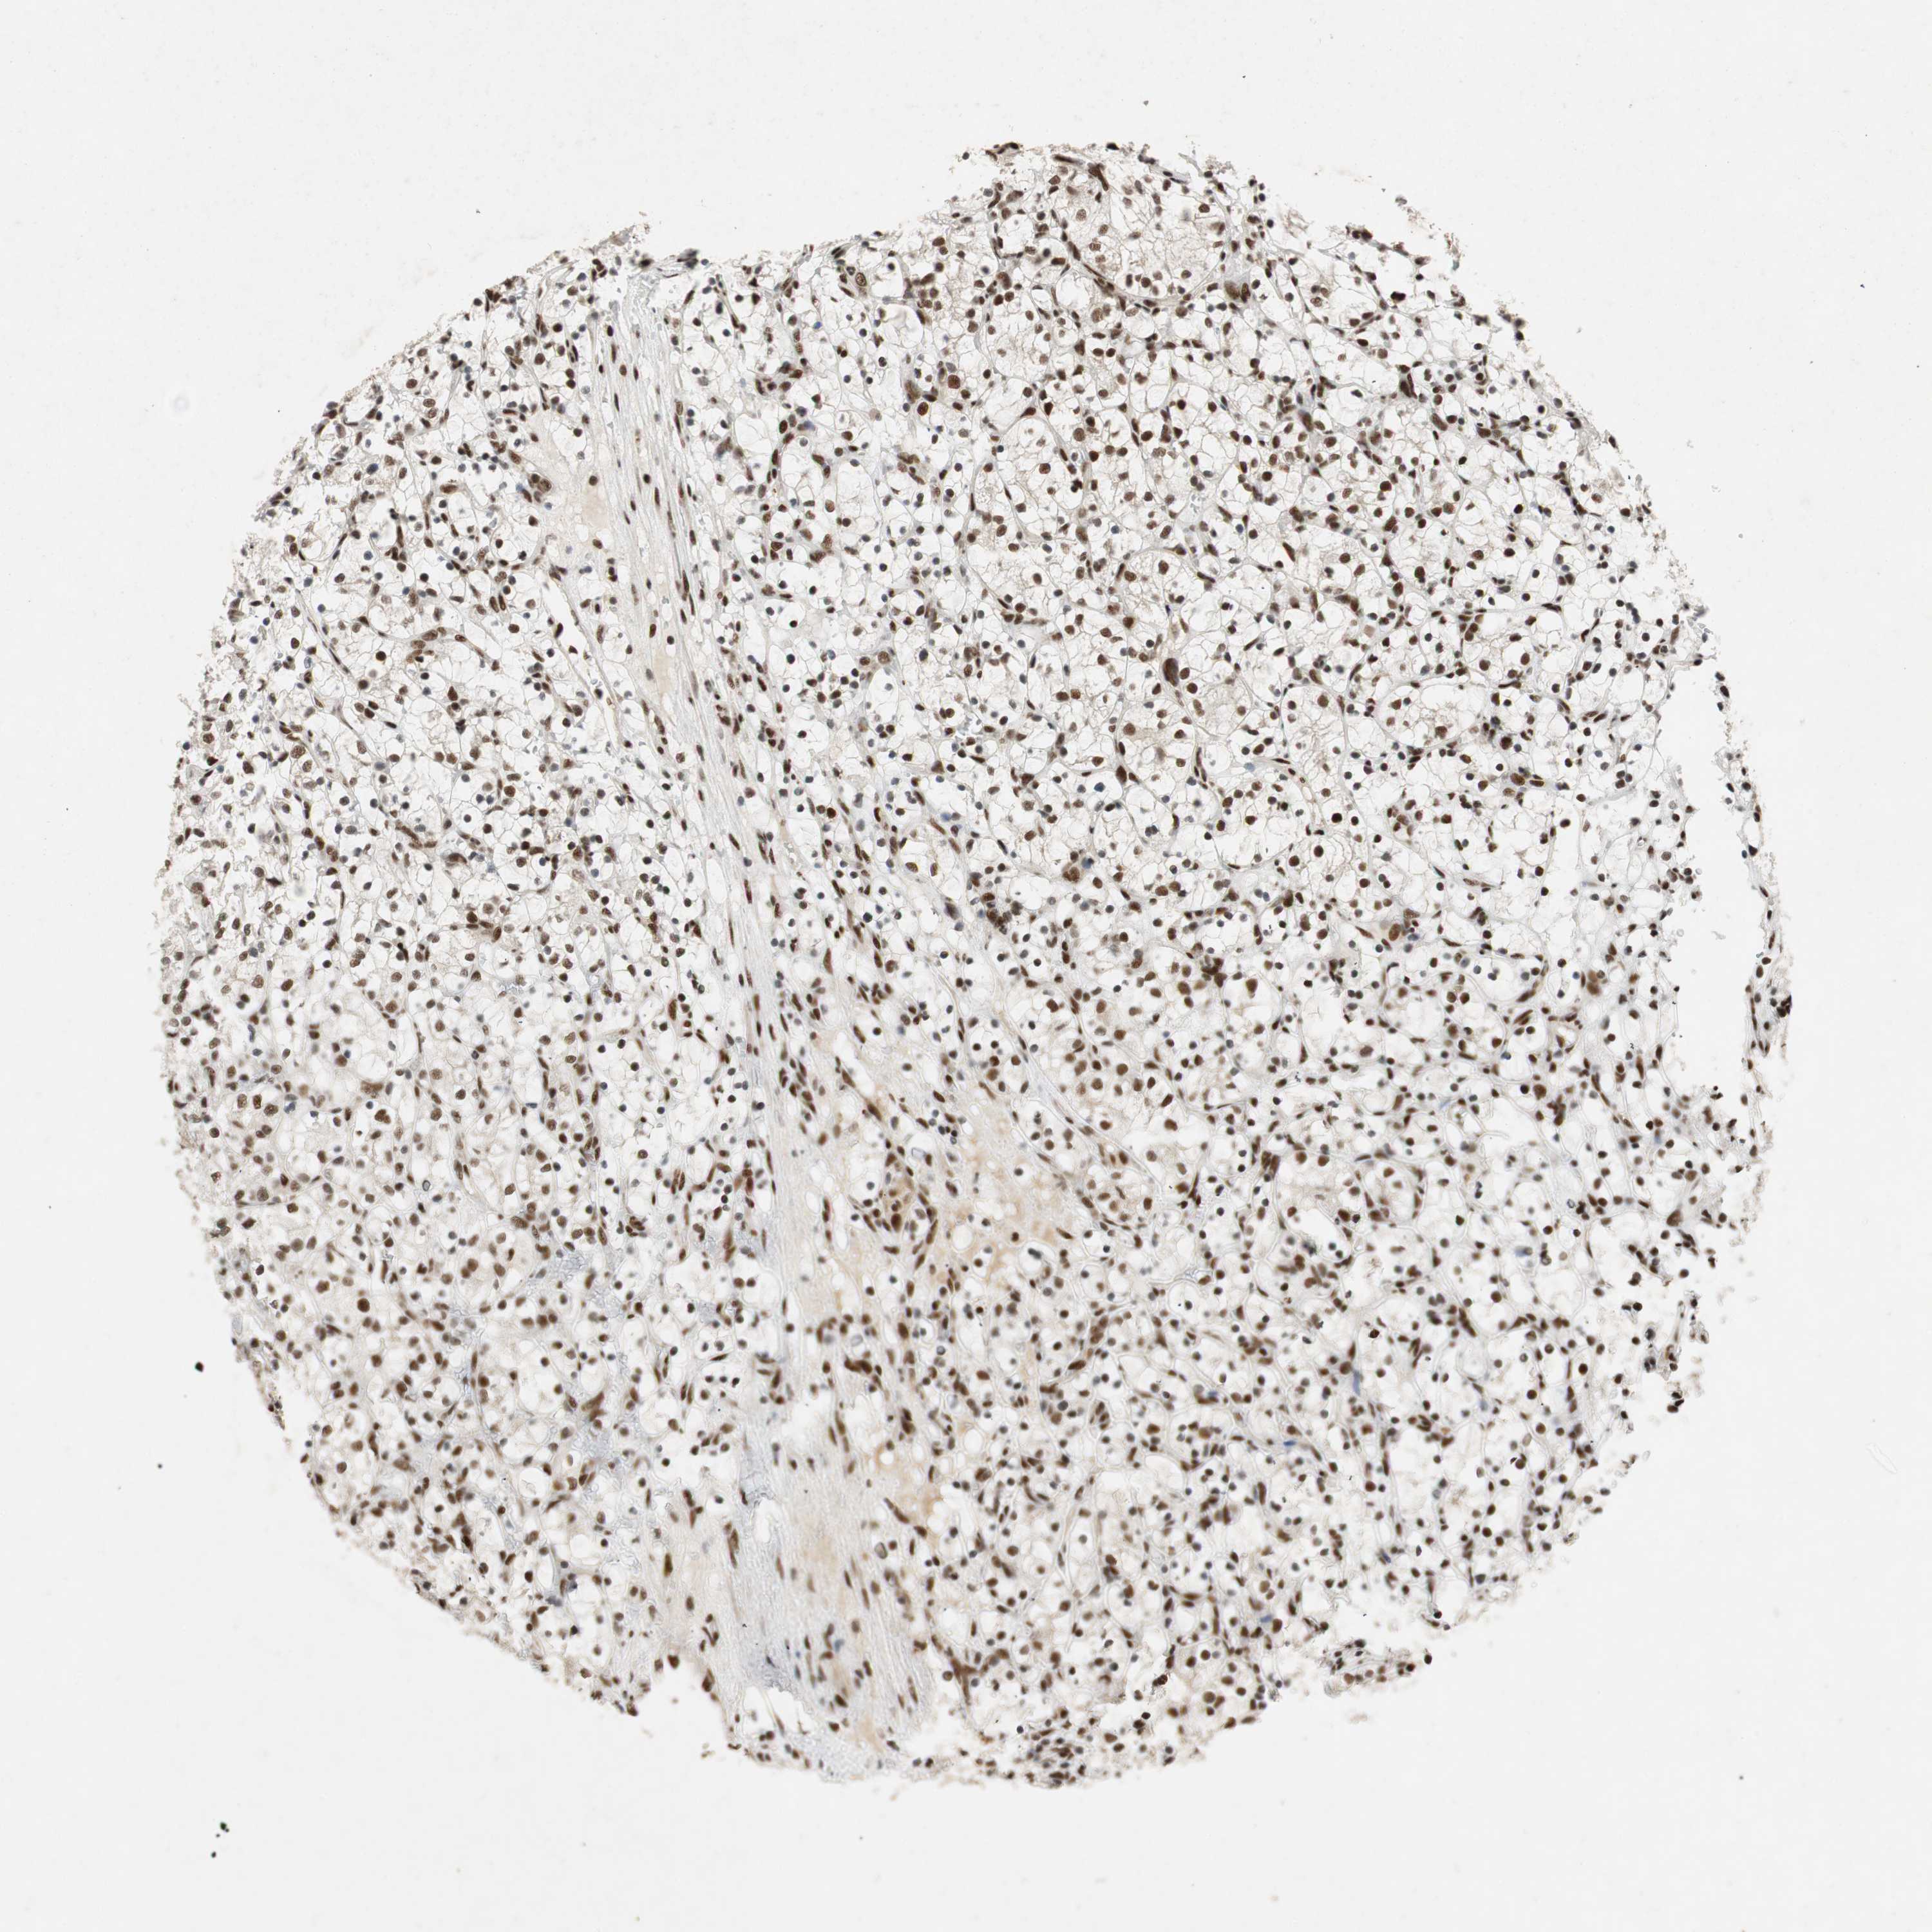

KIDNEY RENAL PAPILLARY CELL CARCINOMA (TCGA) - Interactive survival scatter ploti

The Survival Scatter plot shows the clinical status (i.e. dead or alive) for all individuals in the patient cohort, based on the same data that underlies the corresponding Kaplan-Meier plots. Patients that are alive at last time for follow-up are shown in blue and patients who have died during the study are shown in red.

The x-axis shows the expression levels (FPKM) of the investigated gene in the tumor tissue at the time of diagnosis. The y-axis shows the follow-up time after diagnosis (years). Both axes are complimented with kernel density curves demonstrating the data density over the axes. The top density plot shows the expression levels (FPKM) distribution among dead (red) and alive patients (blue). The right density plot shows the data density of the survived years of dead patients with high and low expression levels respectively, stratified using the cutoff indicated by the vertical dashed line through the Survival Scatter plot. This cutoff is automatically defined based on the FPKM cutoff that minimizes the p-score. The cutoff can be changed by dragging the vertical line or by entering a cutoff value in the square labeled "Current cut-off".

Under the Survival Scatter plot the p-score landscape (black curve; left axis) is shown together with dead median separation (red curve; right axis). Dead median separation is the difference in median mRNA expression between patients who have died with high and low expression, respectively. It is calculated as follows: median FPKM expression of dead patients with high expression - median FPKM expression of dead patients with low expression. This is intended to aid the user in visually exploring custom cutoffs and the associated p-scores and dead median separation.

Individual patient data is displayed and can be filtered by clicking on one or more of the category buttons on the top of the page. Categories describing expression level and patient information include: high, low, alive, dead, female, male and tumor stages. The scale of the x-axis can be toggled between linear and log-scale by clicking on the "x log" button. Mouse-over function shows TCGA ID, patient information and mRNA expression (FPKM) for each patient.

& Survival analysisi

Kaplan-Meier plots summarize results from analysis of correlation between mRNA expression level and patient survival. Patients were divided based on level of expression into one of the two groups "low" (under cut off) or "high" (over cut off). X-axis shows time for survival (years) and y-axis shows the probability of survival, where 1.0 corresponds to 100 percent.

NCBP3 is potential prognostic, high expression is favorable in Kidney Renal Papillary Cell Carcinoma (TCGA)

Best expression cut offi

Based on the FPKM value of each gene, patients were classified into two groups and association between prognosis (survival) and gene expression (FPKM) was examined. The best expression cut-off refers the FPKM value that yields maximal difference with regard to survival between the two groups at the lowest log-rank P-value. Best expression cut-off was selected based on survival analysis .

When clicking on this number, the vertical dashed line indicating cut-off, the interactive survival plot, and the Kaplan-Meier curve will be adjusted to show results based on the best expression cut-off.